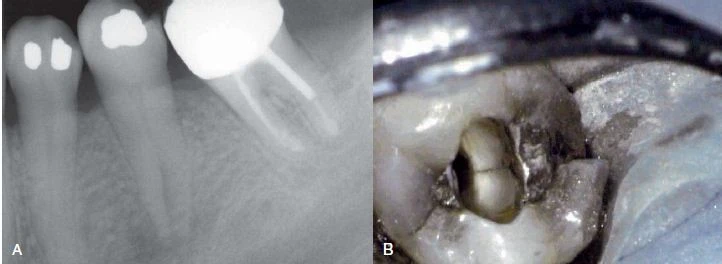

Hình 3. Nhiễm trùng tuỷ răng tái phát sau điều trị nội nha có thể là do nứt dọc chân răng

Đánh giá miếng trám/phục hình trên răng

Răng mang miếng trám nhỏ hoặc không mang miếng trám, không có sâu răng nhưng tuỷ răng chết thì khả năng nghi ngờ cao rằng bị nứt dọc chân răng. Ngoại trừ những trường hợp chấn thương khớp cắn, bệnh lý hệ thống (như nhiễm Herpes Zoster trong miệng), hoặc phẫu thuật vô tình làm chết tuỷ răng (như phẫu thuật xoang, phẫu thuật chỉnh hình, nhổ răng và cấy chuyển răng), nứt dọc chân răng cũng là một trong những lý do khiến răng chết tuỷ. Một răng có bệnh lý nội nha tái phát, răng này trước đây đã được đóng chốt và là răng trụ của một cầu răng vói thì cũng có thể nghi ngờ do nứt dọc chân răng. Lực xoắn trong quá trình ăn nhai tác động lên cầu vói và lực nhún có thể tạo áp lực lên chân răng dẫn đến nứt dọc. Các triệu chứng diễn ra dai dẳng ở một răng mang miếng trám trong thân răng cũng gợi ý trường hợp nứt dọc chân răng. Nhìn chung thông thường sẽ có lý do khiến răng chết tuỷ hoặc đau. Bác sĩ cần đánh giá điều trị phục hồi răng đang có, tìm lý do răng chết tuỷ hoặc các triệu chứng khác, và trong các chẩn đoán phân biệt cần bao gồm cả trường hợp nứt dọc chân răng.

Hình 5. Răng không mang miếng trám hoặc mang miếng trám nhỏ, răng không sâu răng hoặc sâu nhỏ nhưng tuỷ răng bị hoại tử.

Hình 6. Răng đã điều trị nội nha là một phần của phục hình cầu răng vói